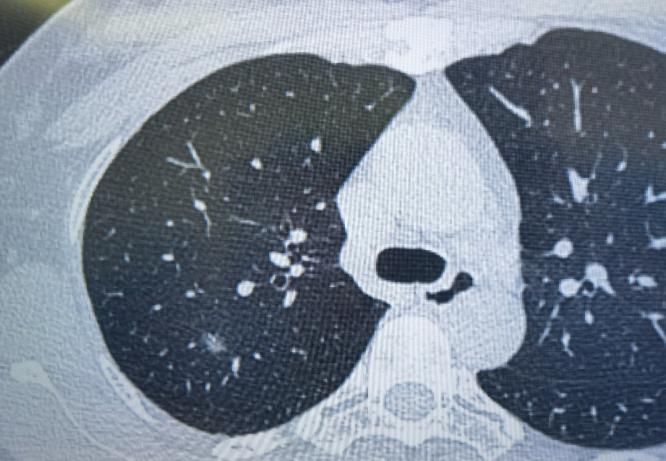

朋友们!别一看到“肺结节”几个字就紧张!其实在检查中发现肺结节非常普遍,绝大多数都和炎症有关,真正由肿瘤引起的情况极少。 肺结节本身是一个影像上的描述,不代表就是不好的东西。所以查出肺结节后,先别急着做手术,不妨给自己一点观察的时间。 一般来说,肺结节可能有以下几种情况: 1、急性炎症引起的结节,可以用消炎药。比如最近正好有发烧、咳嗽,同时查出了肺结节,这很可能是呼吸道感染导致的。 按照医生建议吃一段时间的消炎药,把细菌控制住,结节很可能就慢慢消失了。 这种炎症期的结节,在CT上常常表现为边缘模糊、不太规则,有时候像一小片云雾。 2、有些炎症结节,不用药也可能自己消失。当我们免疫力下降,或者接触的细菌比较多时,肺部可能出现局部炎症。 但如果注意休息、提高抵抗力,身体里的免疫细胞是有能力把这些细菌清除掉的,结节也就随之消散了。 3、还有一些结节是炎症吸收后留下的“痕迹”,就像皮肤受伤后结的疤,已经稳定了。这种陈旧性结节,吃消炎药通常也消不掉,重点就不是用药,而是定期复查、观察变化。 所以,查出肺结节先别慌,大多数情况下它并不可怕。平时注意保持健康生活习惯——吃好、睡好、心情放松,让免疫力维持在良好状态,就是对我们肺最好的保护。[玫瑰][谢谢]胸外科乔贵宾医生肺结节[超话]